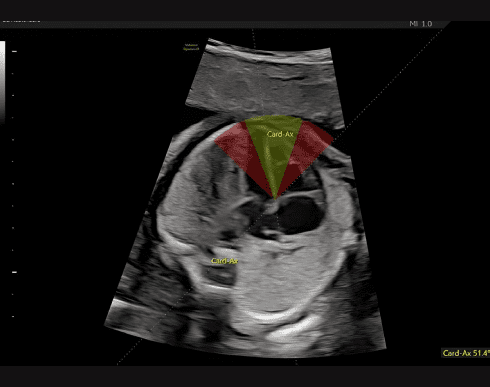

Функція Fetal HS™

Спрощує оцінку серця плода, надаючи поетапний алгоритм, який використовує штучний інтелект для визначення положення плода та нормальної анатомії серця плода за допомогою зображень чотирьох камер серця, трьох судин та вісі серця.